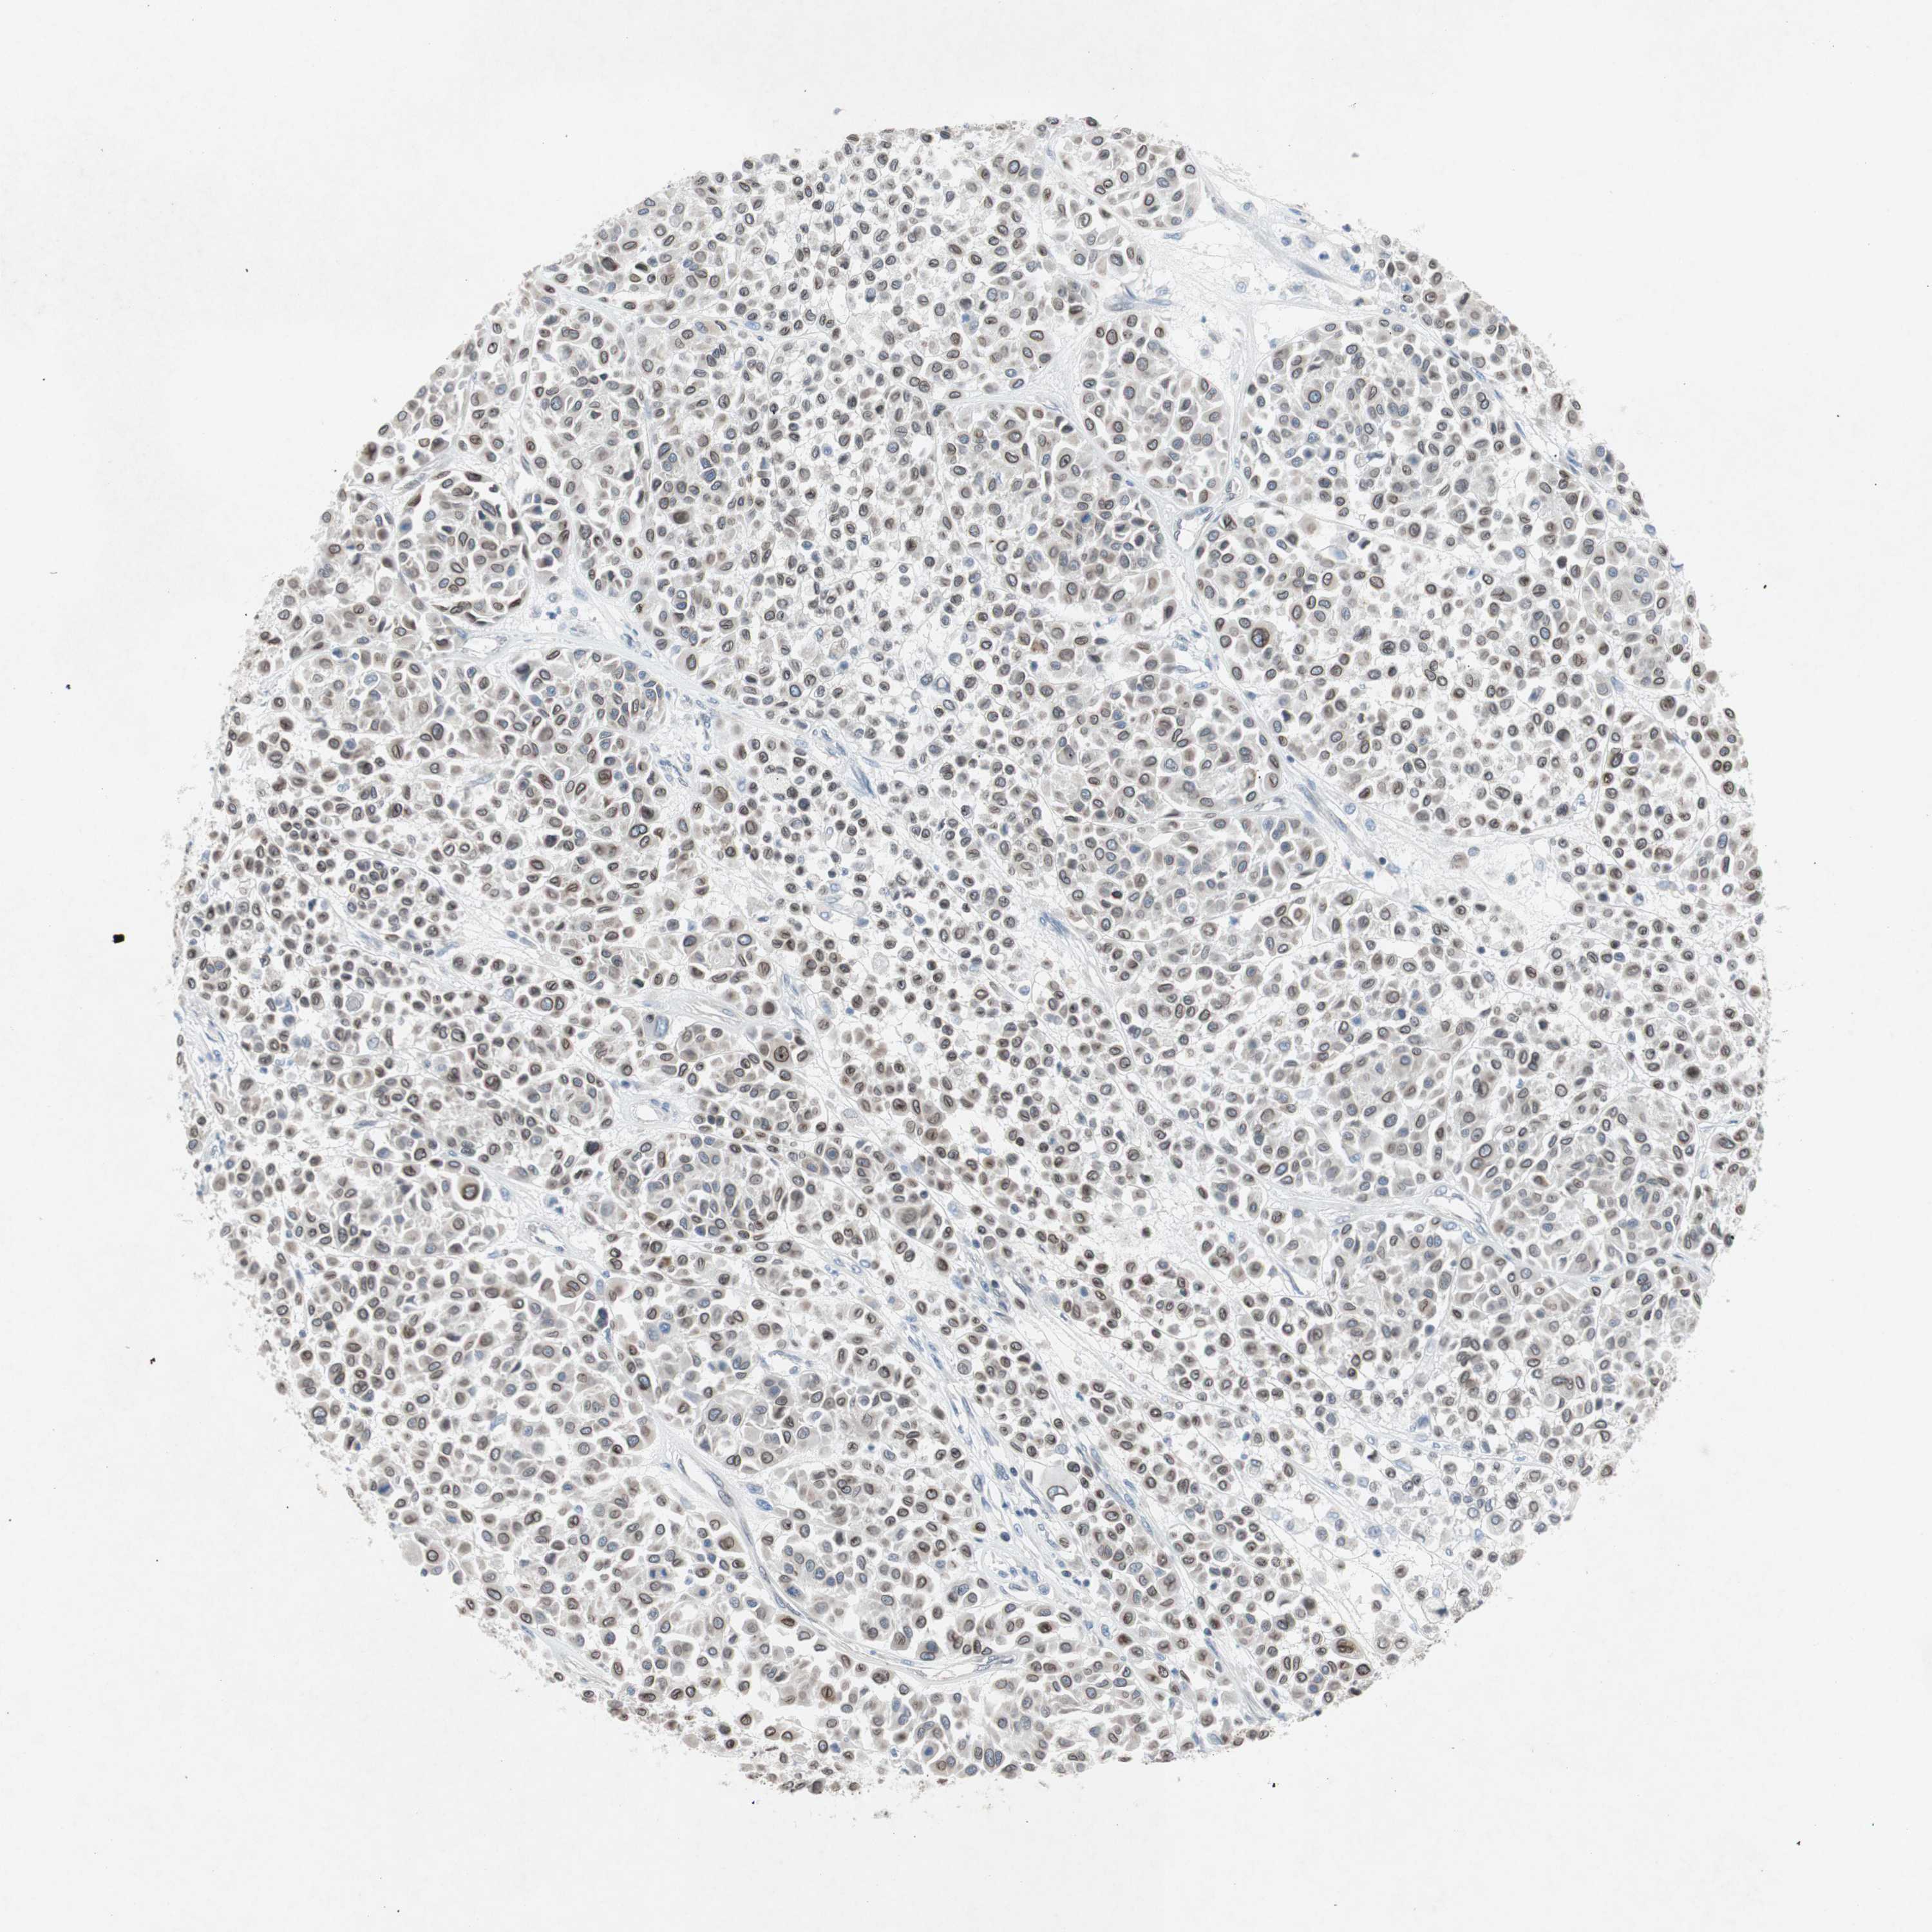

MELANOMA - Protein expressioni

A mouse-over function shows sample information and annotation data. Click on an image to view it in a full screen mode. Samples can be filtered based on level of antibody staining by selecting one or several of the following categories: high, medium, low and not detected. The assay and annotation is described here.

Antibody stainingi

Antibody staining in the annotated cell types in the current human tissue is reported as not detected, low, medium, or high, based on conventional immunohistochemistry profiling in selected tissues. This score is based on the combination of the staining intensity and fraction of stained cells.

Each image is clickable and will lead to virtual microscopy that enables deeper exploration of all samples and also displays staining intensity scores, fraction scores and subcellular localization as well as patient and tissue information for each sample.

Antibody HPA001056

Antibody CAB005081

Staining

High

Medium

Low

Not detected

Intensity

Strong

Moderate

Weak

Negative

Quantity

>75%

75%-25%

<25%

None

Location

Nuclear

Cytoplasmic/membranous

Cytoplasmic/membranous,nuclear

Malignant melanoma, NOS

Malignant melanoma, Metastatic site